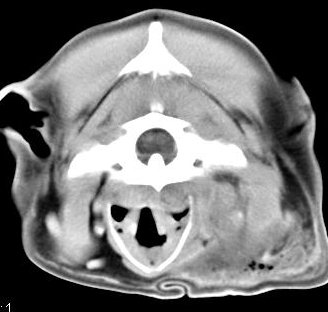

imágenes de TC en el perro | ||||||||||

ejemplo de imágenes de TC en el perro. Nótese la celulitis en la región parotídea izquierda | ||||||||||